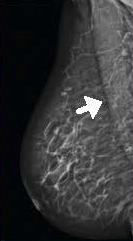

Planmed Clarity™2D – передовая система цифровой визуализации для скрининга и маммографической диагностики. Аппарат максимальным образом оптимизирован для обнаружения рака молочных желёз на ранней стадии. Оборудование легко трансформируется из системы с 2D проекцией в высокоэффективную диагностическую систему с функцией томосинтеза (опционально).

- максимальный обзор тканей груди во всех традиционных проекциях маммографии благодаря запатентованной системе MaxView™;

- чёткое представление на мониторах тончайших тканей и микрокальцификаций благодаря технологии Continuous-Sync-and-Shoot™;